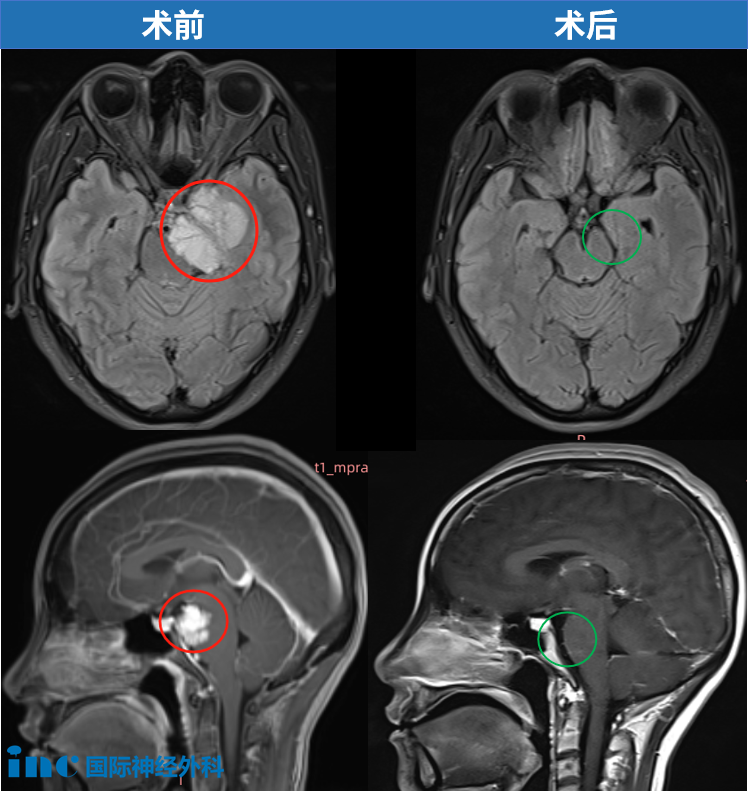

此后,李女士在家人陪同下返回当地医院接受肿瘤切除手术。医生为其切除部分肿瘤,眶内脑膜瘤包绕视神经部分未予切除。术后病理检查证实为WHO I级脑膜瘤。

福教授指出,从两次MRI对比来看,肿瘤情况基本稳定,未见明显生长。因此他建议暂不采取任何积极干预,而是6个月后再次复查MRI,密切观察肿瘤是否有增大或扩散趋势。